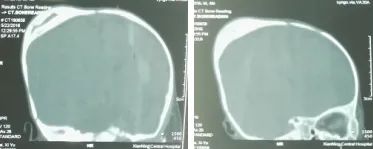

甚至出现钙化,就像下面这张图,在原本的头颅上,又形成了一个蛋壳一样的壳子,也有叫「双层头骨」。

不抽的话,就是未来形成了「双层头骨」,会影响头部发育,可能要面临一次全麻的手术。